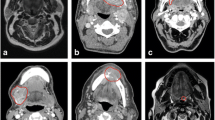

Consisting of a massive sub-partitioning of the PCR mixture into thousands of nanoliter droplets through a water-in-oil emulsion, ddPCR represents an enrichment strategy that allows for the detection of low-level mutations by amplification of single DNA molecules [4]. DNA samples (together with ddPCR Mastermix, primer, and probes in a final volume of 20 µL) and droplet generator oil are loaded into the wells of the droplet generator cartridge. A vacuum ensures that both samples and oil pass through the microfluidic circuits to form a dispersion of 1-nL droplets. In each well, the 20-µL mixture of sample and reagents is divided into 20,000 highly uniform droplets or partitions. These droplets are stabilized by the use of surfactant chemistry. Once transferred to a 96-well PCR plate, amplification is carried out in a conventional thermal cycler [4]. Since the sample is compartmentalized into single droplets, it is considered that an independent PCR reaction takes place in each droplet [35]. Subsequently, the plate is introduced into a droplet reader, where droplets are aspirated from the wells and pass through a two-color detector. Depending on their fluorescence amplitude, droplets are classified as positive or negative using a binary threshold (one positive, zero negative) that gives ddPCR its name of “digital” [4] (Fig. 1). The known droplet volume and the proportion of positive droplets relative to the total number of droplets are used to estimate the target concentration applying a Poisson correction. This is considered a form of “absolute quantification” that makes calibration curves unnecessary for ddPCR [4, 7, 36]. The limit of blank (LOB) and the limit of detection (LOD) for each ddPCR assay have to be determined [37]. LOB is defined as “the frequency of positive droplets measured in normal control DNA samples without mutant DNA present” [37], whereas the LOD is defined as “the true mutant concentration within a sample that will be detected within stated α (false positive) and β (false negative) error limits” [38]. A detailed method for the determination of LOD in ddPCR assays has already been described [38]. In 2013, an article providing some basic guidelines for reporting the results of quantitative ddPCR experiments was published [36]. Among these detailed recommendations, which might be of help to standardize experimental protocols, the necessity of including appropriate controls is highlighted. Thus, negative controls are mandatory for monitoring false-positive reactions, which could be derived from non-specific binding of probes, primer dimer formation, or cross-contamination between samples. A threshold must be set in order to distinguish positive from negative partitions and determine false-positive and false-negative rates. A wild-type (WT) control containing exclusively the wild-type sequence should also be included. In the case of rare event detection assays, the use of controls with different known proportions of wild-type and mutant sequences is also recommended [36].

Representative 2D scatter plot of a ddPCR result, corresponding to KRAS G13D-mutated plasma from a CRC patient analyzed using the QX200™ Droplet Digital™ PCR System (Bio-Rad). The y-axis shows the fluorescence amplitude of the FAM probe, designed to hybridize only to the mutant allele (blue). The HEX probe, which hybridizes only to the wild-type reference allele (green), is plotted on the x-axis. Double-positive droplets carrying both types of molecules are represented in orange, while double-negative droplets (no amplification) are shown in grey. CRC colorectal cancer, ddPCR droplet digital PCR